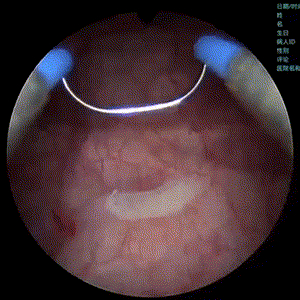

APL-1706202310月举行的国际泌尿外科学会年会(SIU)上以口头报告形式首次发布Ⅲ期临床试验数据,临床结果入选Late-Breaking AbstractLBA)。该研究证实了在中国患者中,APL-1706联合蓝光膀胱镜(BLCbluelight cystoscopy)在膀胱癌检测方面优于白光膀胱镜 (WLCwhite light cystoscopy),尤其是原位癌(CIScarcinoma in situ)的检出,并且其耐受性良好。

蓝光下可以有效提高CIS的检出率